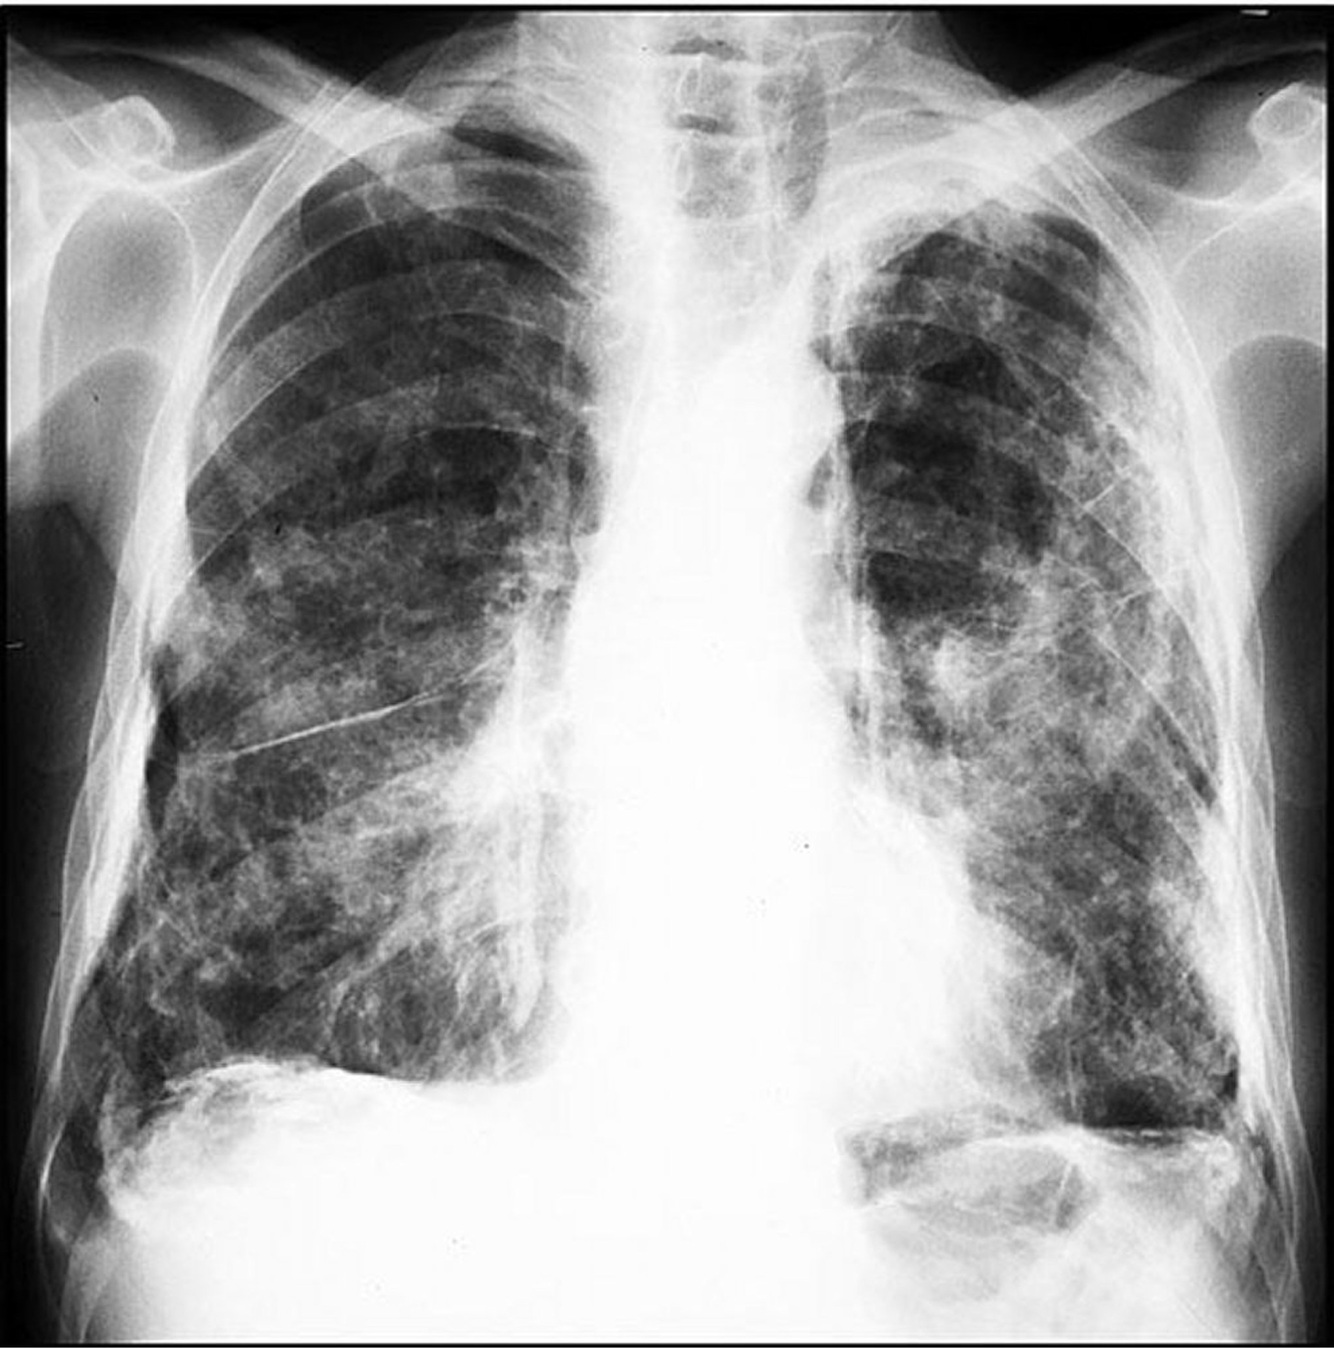

Quais são os achados radiológicos típicos da asbestose na radiografia de tórax?

• Opacidades irregulares ou reticulares, predominando nas bases pulmonares

• Placas pleurais associadas (calcificadas ou não)

• Espessamento pleural difuso, a doença relacionada ao asbesto mais prevalente

• Atelectasia redonda com distorção vascular em cauda de cometa

As alterações radiológicas da asbestose podem ser indistinguíveis das alterações da fibrose pulmonar idiopática. Verdadeiro ou falso?

Verdadeiro.

As radiografias de tórax na asbestose podem apresentar opacidades reticulares e irregulares similares às encontradas na fibrose pulmonar idiopática, tornando os dois quadros radiologicamente indistinguíveis em alguns casos.